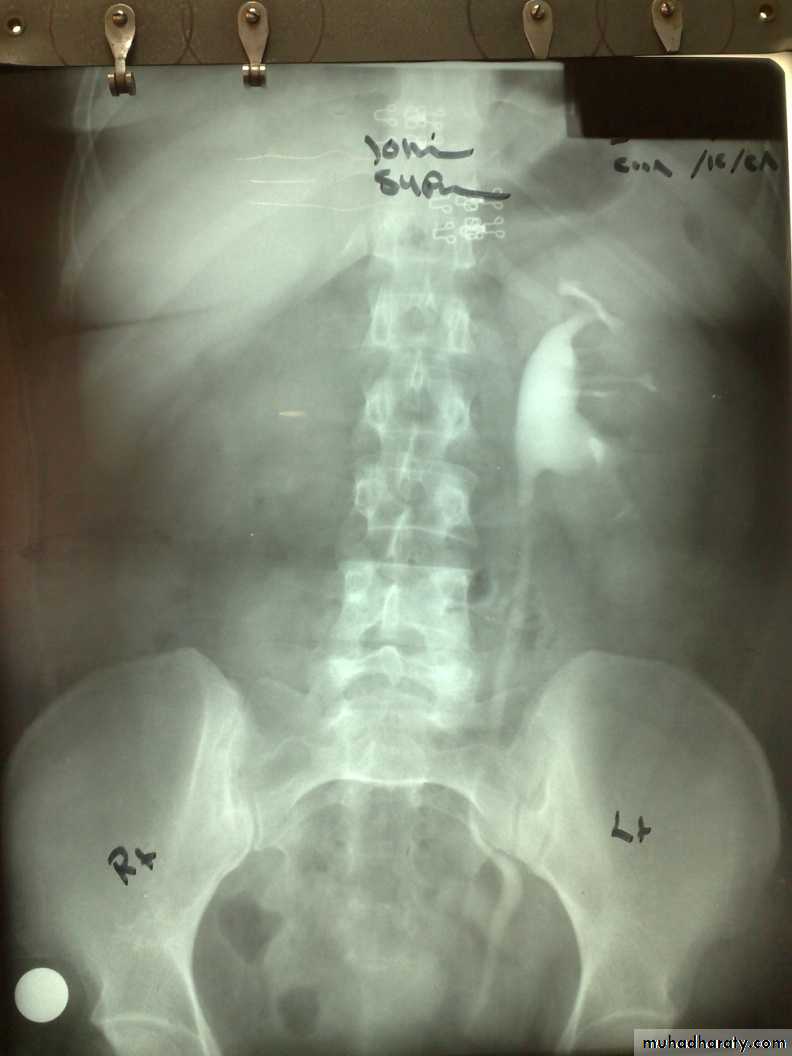

KUB.

Non visualization of the Rt. Kidney either due to early obst. Or type 5 renal injuryWhat's this imaging study?What the abnormal finding?